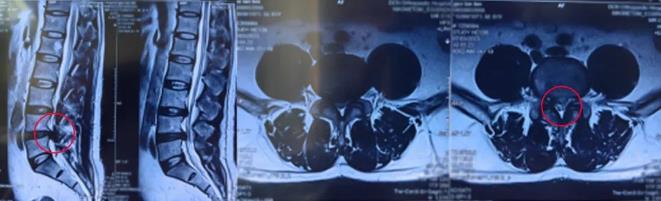

骨科科普|腰椎間盤突出疼痛半年,椎間孔鏡技術一朝解決

腰椎微創手術 随著(zhe)社會經(jīng)濟的發(fā)展,大家的工作強度逐漸增加,腰腿痛患者也越來越多。大家都(dōu)知道(dào)腰椎間盤突出症這(zhè)個疾病,但是怎麼(me)治療呢?按摩?針灸?微創?開(kāi)放?...